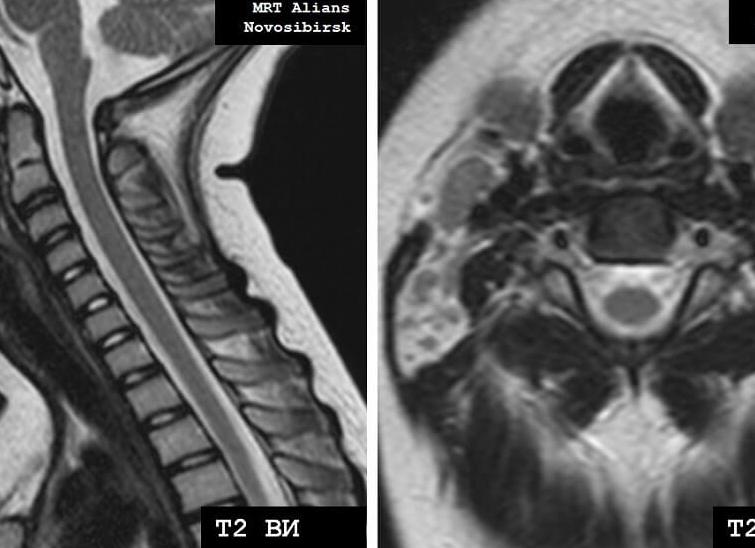

Гормональным сбоем у женщины называется результат воздействия на организм различных факторов, который приводит к нарушению работы гормональной системы на разных ее уровнях. К внешним причинам патологии относятся физические и психологические нагрузки (атмосфера в семейной и профессиональной жизни). К внутренним — состояние здоровья (хронические заболевания ). Определить гормональный сбой у женщины можно с помощью анализа крови.